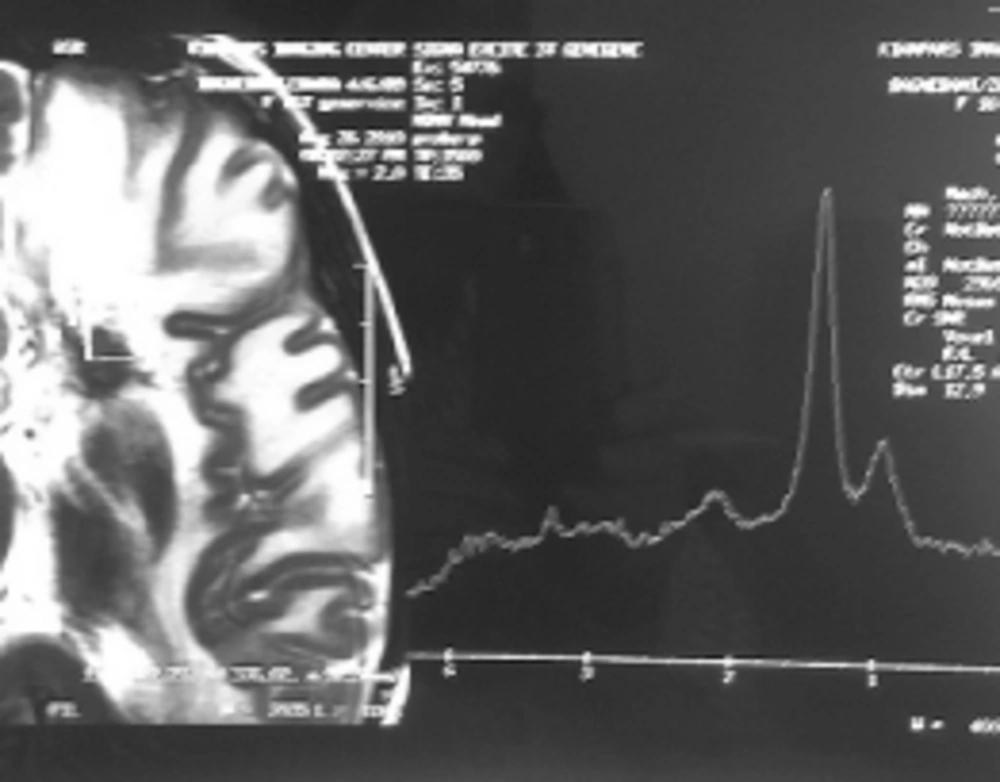

Case 1: A 15-year-old girl with acute lymphoblastic leukemia diagnosed in 2010 was receiving maintenance treatment. Three weeks ago, she referred to a hospital with headache, nausea and vomiting. CT scan of the brain demonstrated low density of mass like a lesion of the left parietal lobes cortico medullary junction accompanies with mild vasogenic edema and no enhancement after contrast media administration. Findings were non specific in CT scan. MRI was applied and on the obtained images there was left parietal corticomedullary junction intermediate signal intensity lesion with vasogenic edema on T2 which as a bright intermediated signal in T1 and low signal intensity peripheral edema (Figure 1A, 1B), follow in contrast media administration remarkable enhancements of lesions are seen (Figure 1C). These findings were compatible with toxoplasmosis and lymphoma. MRI spectroscopy (MRS) was done and increasing of lactate and lipid and low choline were seen in the spectrum of MRS which are specific for necrotizing abscess (Figure 2). Ig M antibody against Toxoplasma by Chemiluminesans (Roche kit) was 8 IU/mL (reference range: non reactive < 0.8; intermitant 0.8- 1; reactive > 1) and Ig G was 4 IU/mL (reference range: Non reactive ˂ 1; intermitant 1- 3; reactive ˃ 3). The patient prescribed with pyrimethamin, sulfadiazine and leucoverin.